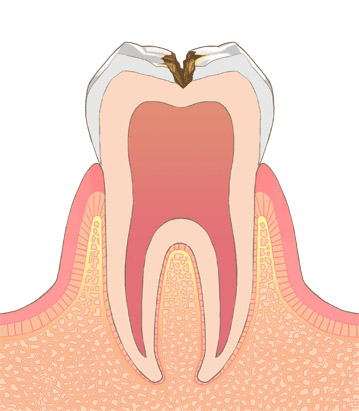

むし歯がエナメル質の内側の象牙質に達したものです。象牙質はエナメル質により軟らかい組織なので、むし歯の進み方が速くなります。